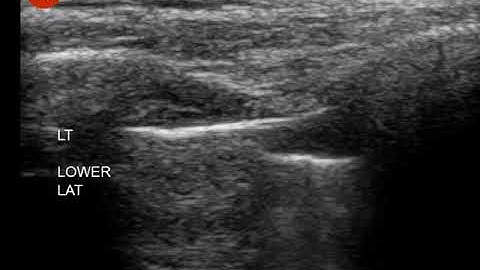

Pneumothorax: Ultrasound Image Interpretation